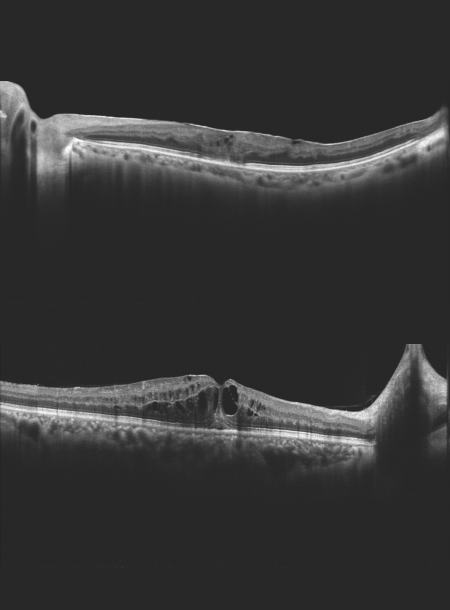

• Висока якість ОКТ-зображення

• Глибина сканування 3 мм показує деталізоване зображення склоподібного тіла, сітківки та судинної оболонки

High quality OCT image

Spectral domain OCT

Super luminescent diode (SLD), 840 nm